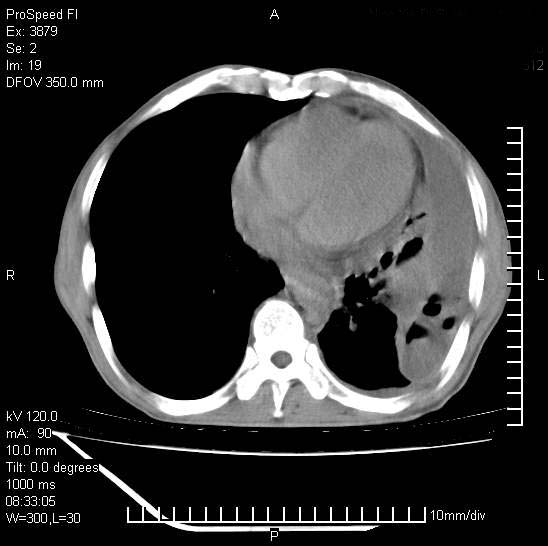

以下是引用37度在2008-6-6 11:20:00的发言:[br]1.包裹性积液,多考虑结核性;[br]2.穿刺术后改变。

以下是引用312nanyang在2008-6-6 15:12:00的发言:[br]基本支持楼主意见[br]疑问?左下肺支气管旁的软组织(16层)密度怎么解释?淋巴结还是斜裂胸膜增厚所致?能否增强进一步检查